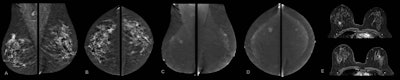

Contrast-enhanced mammography exam of both breasts in two views. In the first two low-energy images (A, B), an ill-defined mass can be seen in the upper outer quadrant of the right breast at the location of a palpable mass in a 52-year-old patient. In the left breast, no relevant abnormalities can be detected. In the recombined images (C, D) of a contrast-enhanced mammography examination, contrast uptake can be appreciated. The recombined images show an irregular enhancing mass in both breasts -- both in the upper outer quadrant. Tissue sampling revealed a bilateral invasive breast cancer of no special type. A breast MRI examination performed prior to surgery also confirmed the presence of two irregular enhancing masses on these contrast-enhanced T1 weighted images (E: top example is the cancer in the right breast; bottom example is the left breast). All images courtesy of Dr. Marc Lobbes, PhD.